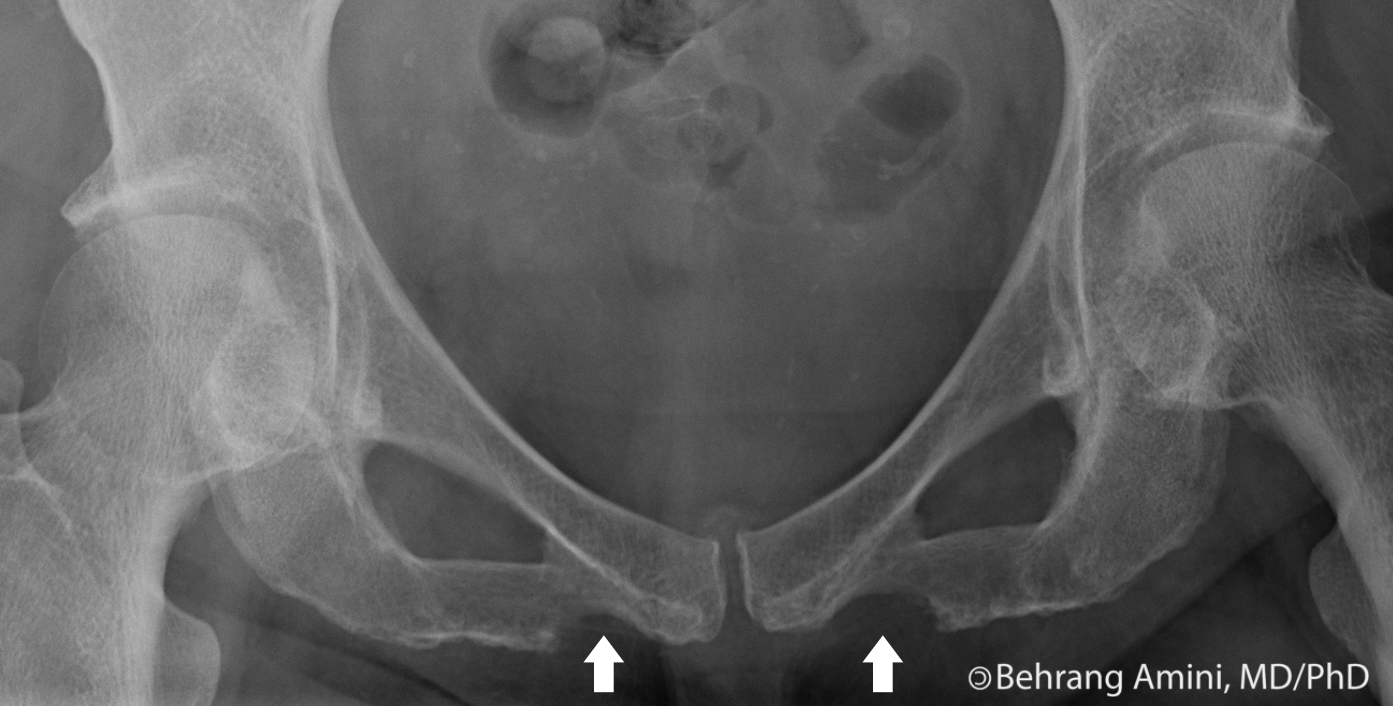

Pathological fractures occur in bones weakened by disease. Fractures of the pubic rami are the most frequent osteoporotic pelvic fracture. These fractures are usually classified as stable injuries and in practice, the discovery of a pubic ramus fracture would not normally generate significant concern 3.

I13.11 obstructive bronchitis (copd) with exacerbation. Closed fracture pelvis, single pubic ramus (disorder). Pubic rami pubic ramus fracture. However, it is important to note that. Please note that there is no difference between a fracture and a break. 27193 (closed treatment of pelvic ring fracture, without manipulation). Pubic rami fractures are common. It forms the inferior border of the obturator foramen and serves as part of the origin for the obturator internus and externus. These fractures are usually classified as stable injuries and in practice, the discovery of a pubic ramus fracture would not normally generate significant concern 3. J34.2 deviated, nasal septum 4. For each site there are six possible code numbers according to whether the neoplasm in question is malignant, benign, in situ, of uncertain behavior, or of unspecified nature. The superior ramus and the inferior ramus. A statistically significant difference was observed between the two groups in pubic discontinuities (fractured group 8/10, nonfractured group 16/330; From the pubis, the inferior pubic ramus. It is likely, however, that the pelvis is subjected to abnormal mechanical loads. S32.519a is an initial encounter code, includes a 7th character and should be used while the patient is receiving active treatment for a condition like fracture of superior rim of. If there is a fracture of one pubic ramus there is almost always a second fracture of the other ramus visible.